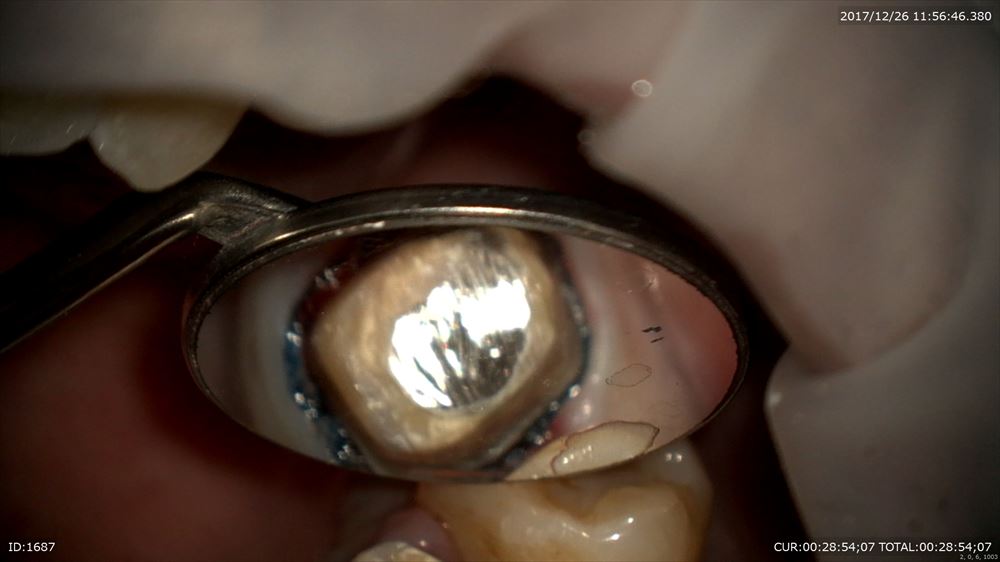

シリコンを使用し採れた型を観察しチエック

倍率をあげて(8倍)チェック歯茎の内部まで流れているか。。

いいね。マイクロスコープがなければ観察できないです。